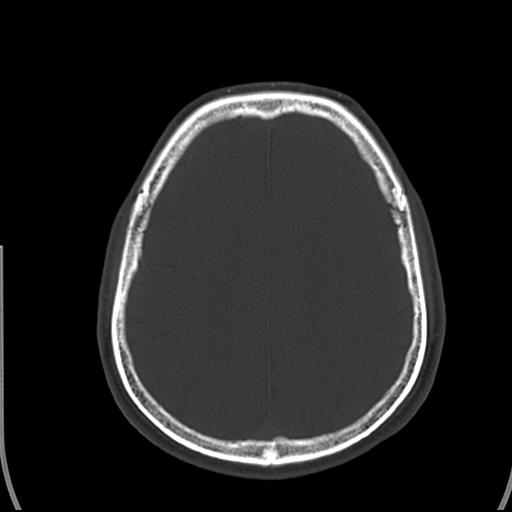

标题: CT25435:头皮下高密度影???

头皮下高密度结节影???临床上在老年男性比较常见。大家看看是什么?成因是? 本例患者,男性,51岁。外伤来诊。无染发史及发根植入史。

这种东西有时要结合触诊和望诊。